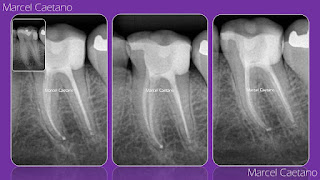

Técnica de Clark: dissociação radiográfica para visualização de todos os canais.

Para adequada e completa visualização de todos os canais radiculares presentes em um dente, o Endodontista frequentemente na sua rotina clínica realiza a famosa Técnica de Clark durante a realização das radiografias periapicais.

Segue como exemplo nesta imagem acima do tratamento endodôntico finalizado em um molar inferior, onde foram realizadas 3 tomadas radiográficas: ortorradial, mesiorradial e distorradial.

Esta técnica radiográfica permite a dissociação dos canais, através de leve alterações no ângulo horizontal de exposição dos Raios-x.